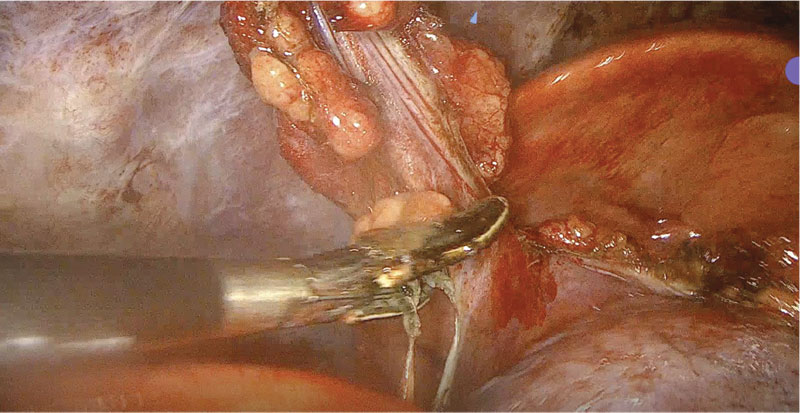

Once the thoracic duct has been identified, dissection immediately dorsal to the aorta is then performed to isolate the thoracic duct (Figure 9). A longitudinal incision is created dorsally to the aorta, carefully avoiding the intercostal arteries to prevent hemorrhage (Figure 10). If an intercostal artery is damaged, ligation can be performed using a vessel sealing device if necessary.

Figure 9. Thoracoscopic dissection is being performed on the thoracic duct. Photo courtesy Dr. Ashley Villatoro

Figure 10. Longitudinal incision created using J-hook cautery immediately dorsal to the aorta, between the intercostal arteries, to better dissect and access the thoracic duct.

Photo courtesy Dr. Ashley Villatoro

Dissection then continues to clear the adventitia from the aorta ventral to the thoracic duct and to clear the dorsal mediastinum ventral to the hypaxial musculature and sympathetic trunks. Once the thoracic duct is freed and all associated branches visualized, ligation can then be performed. Figure 11 illustrates endoclips being applied to the thoracic duct. Alternatively, a vessel sealing device can be used solely, or as in Figure 12, concurrently, to ligate and divide the thoracic duct between endoclips. An en bloc encircling suture can also be performed to ligate the structures between the aorta and the sympathetic trunk.

Figure 11. The thoracic duct (highlighted by ICG) is being occluded using multiple endoclips. Photo courtesy Dr. Ashley Villatoro.

Figure 12. The thoracic duct has been ligated with endoclips, and a Ligasure vessel sealing device is used to ligate and divide between a set of endoclips. Photo courtesy Dr. Sarah Marvel